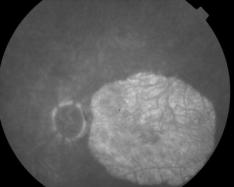

CICATRICE APRES EXERESE CHIRURGICALE DE NEOVAISSEAUX

IM000009.JPG